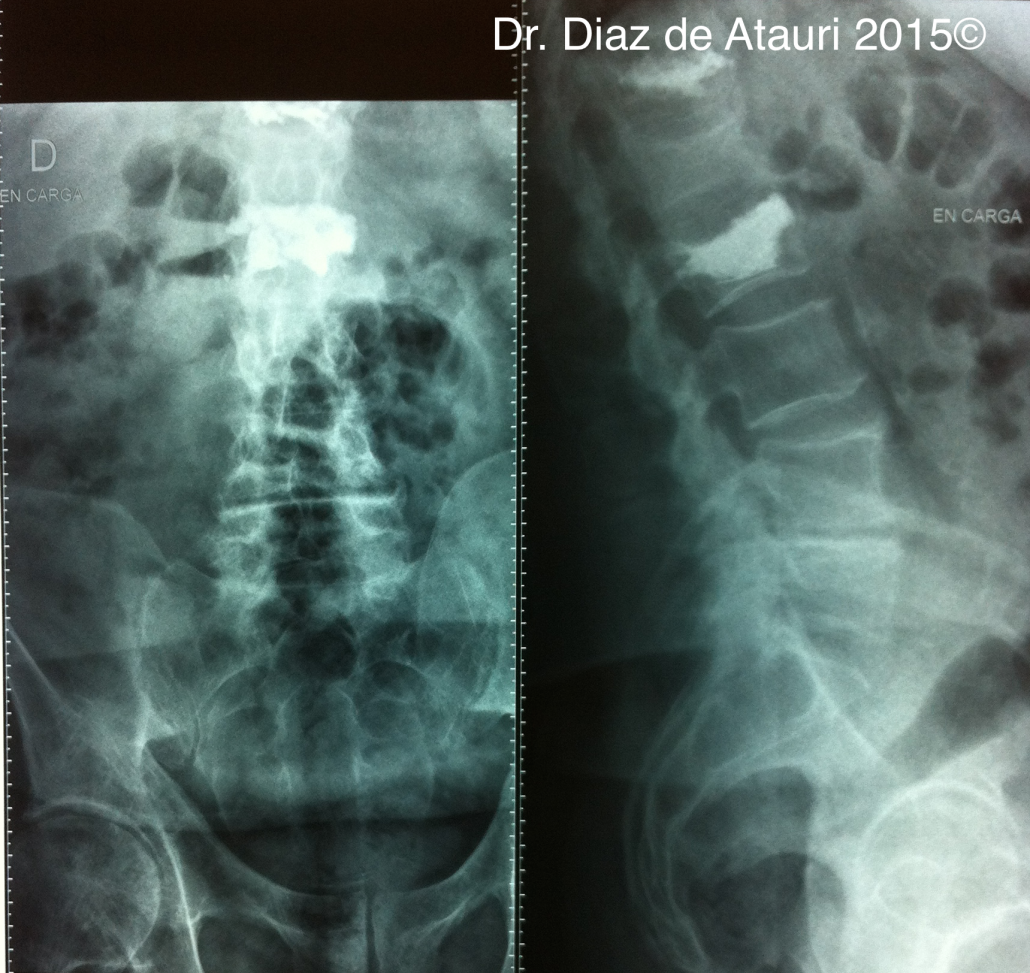

Puedes ver imágenes de una fractura y de la técnica quirúrgica de un caso real del 2015 tras este texto.